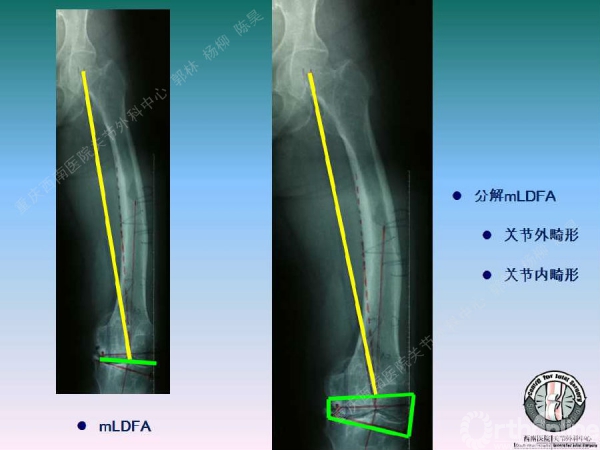

导读:文中,来自重庆西南医院的郭林教授为大家介绍了股骨冠状位关节外畸形的TKA的相关知识,并详细阐述了关节外畸形的概念、诊断、关节内滑移截骨技术等相关内容。

滑移截骨纠正关节外畸形